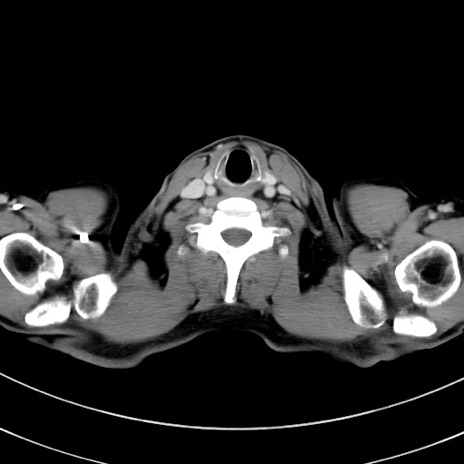

症例8(横断像)

【症例】 60歳代男性

【主訴】 黒色吐物

【現病歴】 4日前から嘔気自覚、2日前の朝食後にも嘔気あり、自分で手で嘔吐反射起こし嘔吐したところ血が混ざっていたため受診。

【既往歴】 5年前汎発性腹膜炎を伴う急性虫垂炎で手術、高血圧、前立腺肥大症、高脂血症

【身体所見】 腹部正中に手術癩痕あり 腹部平坦・軟圧痛なし膨満感あり

【データ】WBC 8400、CRP 4.54